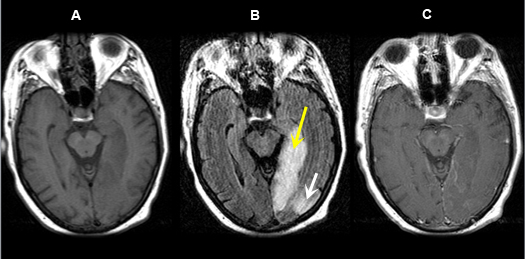

Figure 5 A-C: MR Images

Posterior cerebral artery territory Acute Stroke

Imaging findings: Figure 5 A-C

- Pre-contrast axial T1 wtd. MRI

- Axial flair image

- Post-contrast axial T1 wtd. MRI

Acute infarction is seen involving the left occipital lobe (yellow arrow) and adjacent left temporal lobe (white arrow). The left posterior cerebral artery territory infarction is better seen on flair sequence (Fig. B) than on T1 wtd. pulse sequence (Figs. A, C).